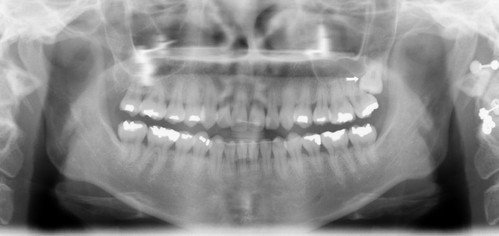

27세 여자 환자 좌측 제2대구치를 발치해야한다는 진단을 받고 상담 중 사랑니를 교정해서 위치시키고 써보자고 얘기했다~